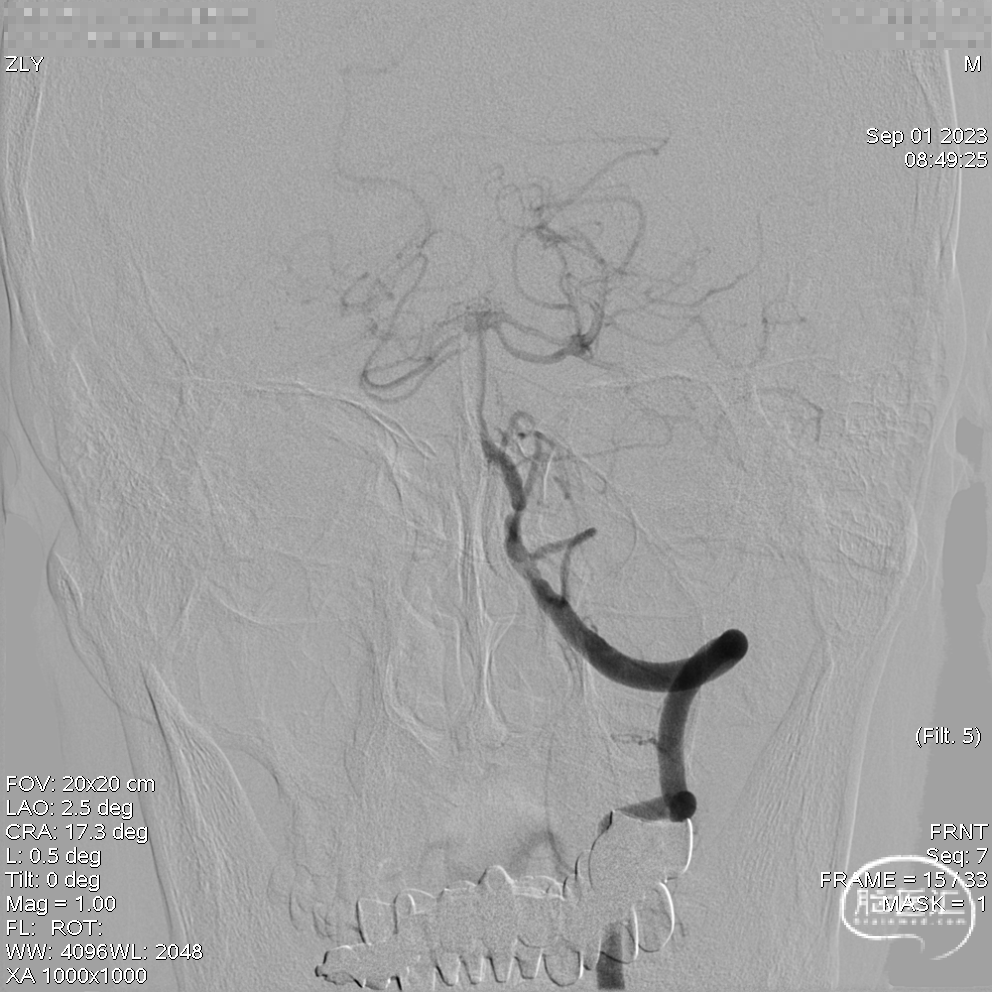

DSA示双侧椎动脉V4段狭窄,右侧为著且合并梭形动脉瘤。

术前DSA。